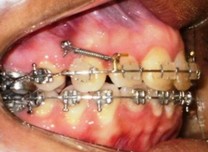

Ortodoncia con microimplantes

Tratamientos de ortodoncia

combinados con la instalación de

microimplantes como refuerzo mecánico.